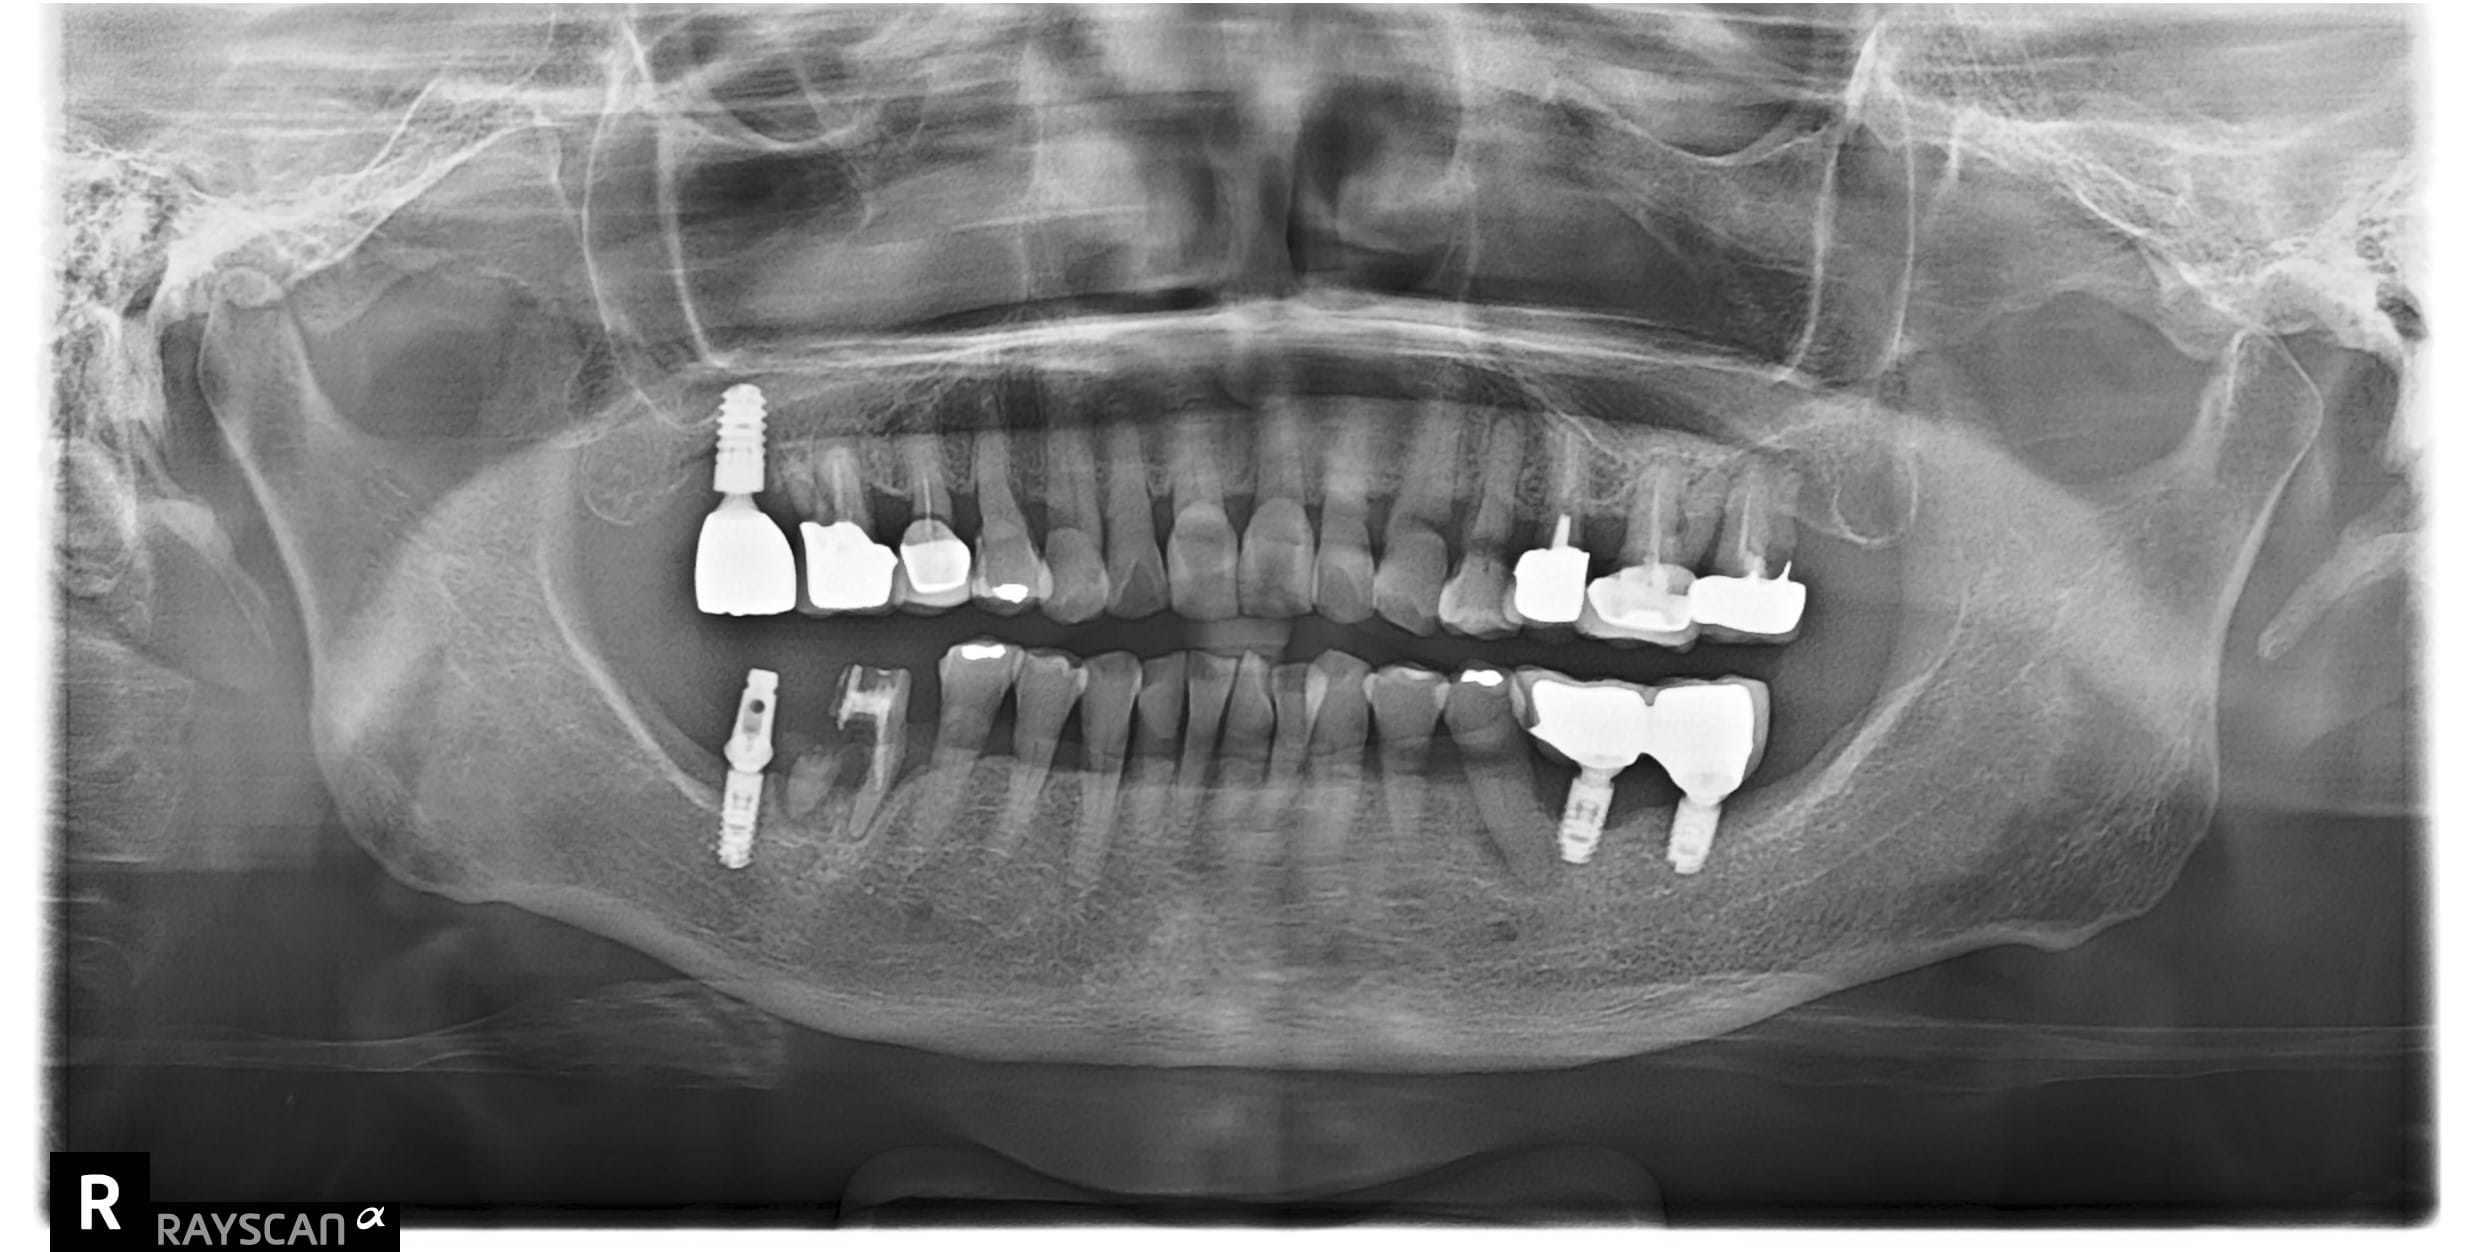

x先生左下第二小臼齒舊牙冠二次蛀牙斷掉,並影響到咬合問題 假牙不密合導致再蛀齒質脆弱咬東西斷,建議即

x先生左下第二小臼齒舊牙冠二次蛀牙斷掉,並影響到咬合問題 假牙不密合導致再蛀齒質脆弱咬東西斷,建議即

c先生因左上第一大臼齒根管後未裝牙套吃東西咬裂,故尋求協助治療。 牙齒裂致根部,需先拔除待傷口1-2

自述#46缺牙十年左右 想植牙改善右下第二大臼齒往前倒的狀況 骨頭狀況良好可直接植牙,等植牙接出後需

左下第一二大臼齒有膿包周囊袋過深,發現牙根斷裂 即拔即種當下清除發炎組織再補骨促進骨整合 左半邊咬合

左上第一小臼齒蛀牙缺損 齒質蛀牙嚴重導致斷裂,骨頭破壞需植入牙根時補骨促進骨整合 待3個月後骨整合完

右下第一大臼齒蛀斷 原右下第一.二大臼齒假牙相連,因右下第一大臼齒蛀牙到根部,導致兩顆假牙脫落,右下